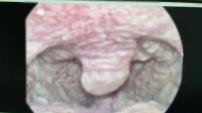

医院耳鼻喉科主任邬忠伟给张先生做检查时,发现他整个咽后壁白茫茫一片,像铺了一层“雪花”。

图源:宁波市北仑区第二人民医院

最终,张先生被确诊为真菌性咽喉炎——罪魁祸首不是细菌,而是白色念珠菌。